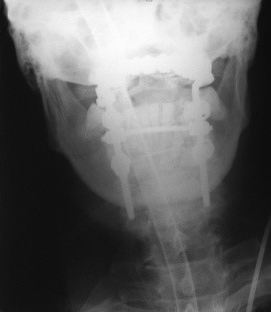

”O·C·A·M” (Occipito-Cervical Anchorage Method) implants are intended for use in the treatment of the occipito-cervical spine from the posterior surgical approach.

”O·C·A·M” stabilizer is based on ”anchors” fixation in occipital bone and cervical spine (lateral masses). The design of ”anchor” provides the strongest and safest fixation of the implant in bone (up to 7 times stronger compared to bone screws) and ensures the durability of the stabilization system. Especially, when used in lateral masses the implant minimizes the risk of contact with the neuro-vascular system (higher risk occurs with transpedicular screws). The system comes in a wide range of hooks and screws, which provide several stabilization options depending on the individual intra-operative case.

5. Possible fixation locations of ”anchor” in lateral masses